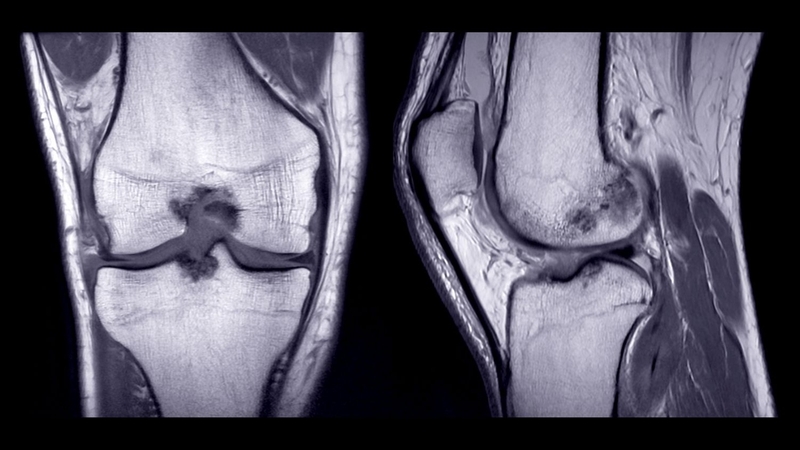

Phù tủy xương dưới sụn là tình trạng tích tụ dịch bất thường bên trong tủy xương gây sưng viêm và đau nhức cho người bệnh. Đây là dạng tổn thương thường gặp khi mắc một số bệnh lý như viêm xương khớp, chấn thương, loãng xương,…

Phù tủy xương dưới sụn có thể khởi phát ở bất cứ vị trí xương nào trên cơ thể, thường gặp nhất là ở các vị trí như khớp hông, đầu gối, mắt cá chân và hiếm gặp ở các chi trên.

Để chẩn đoán phù tủy xương dưới sụn, bệnh nhân sẽ được kiểm tra thể chất và thực hiện các xét nghiệm hình ảnh, bao gồm: